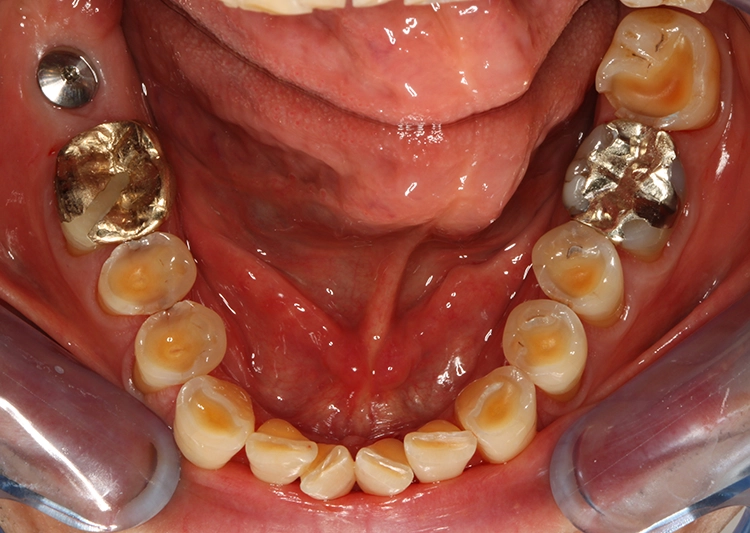

Egger/Wermuth/GrevenRote Ästhetik: Im Ober- und Unterkiefer zeigten sich generalisiert ausgedehnte Rezessionen mit bis zu 8 mm Attachmentverlust vor allem im Bereich der Eckzähne (Miller-Klasse III; Rezessionstyp [RT] 2 [69]. Das Band an keratinisierter Schleimhaut ist durchgehend vorhanden. Die Breite variiert im Eckzahnbereich von 1 mm bis zu 2 mm im Bereich der Unterkieferfrontzähne, der Prämolaren und Molaren (Abb. 1). Die fazialen Rezessionen sind mit approximalem röntgenologischem Attachmentverlust im koronalen Wurzeldrittel (Abb. 2) und Papillenverlust im Bereich zwischen den Kontaktpunkten und der approximalen Schmelz-Zement-Grenze assoziiert (Abb. 1). Der Patient verfügt über eine schmal geformte Oberlippe. Die Lachlinie verläuft mittelhoch (Abb. 3).

Parodontale Gesundheit bei Attachmentverlust, Bruxismus, Erosion. Abbildung 1 sowie 6 bis 9 zeigen den Anfangsbefund als intraoralen Fotostatus.*